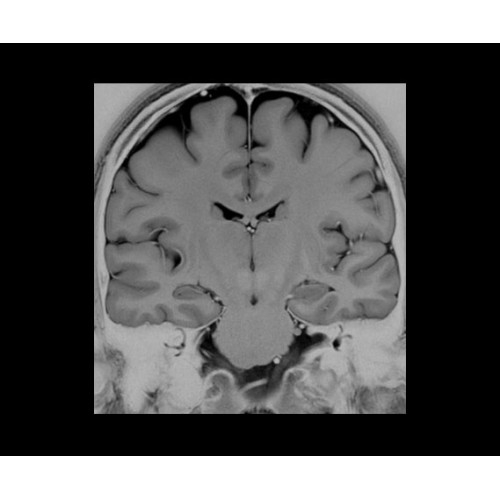

• NeuroWorks — универсальное решение для визуализации анатомии головного мозга, позвоночника, сосудов и периферических нервов с четкой дифференциацией тканей.

• 48-канальная катушка TDI для головы, входящая в базовую комплектацию SIGNA Architect, обеспечивает феноменальную производительность с учетом особенностей каждого пациента. Благодаря гибкому и универсальному дизайну, высокому соотношению сигнал/шум и передовым технологиям визуализации, таким как HyperWorks, учитываются потребности подавляющего большинства пациентов.